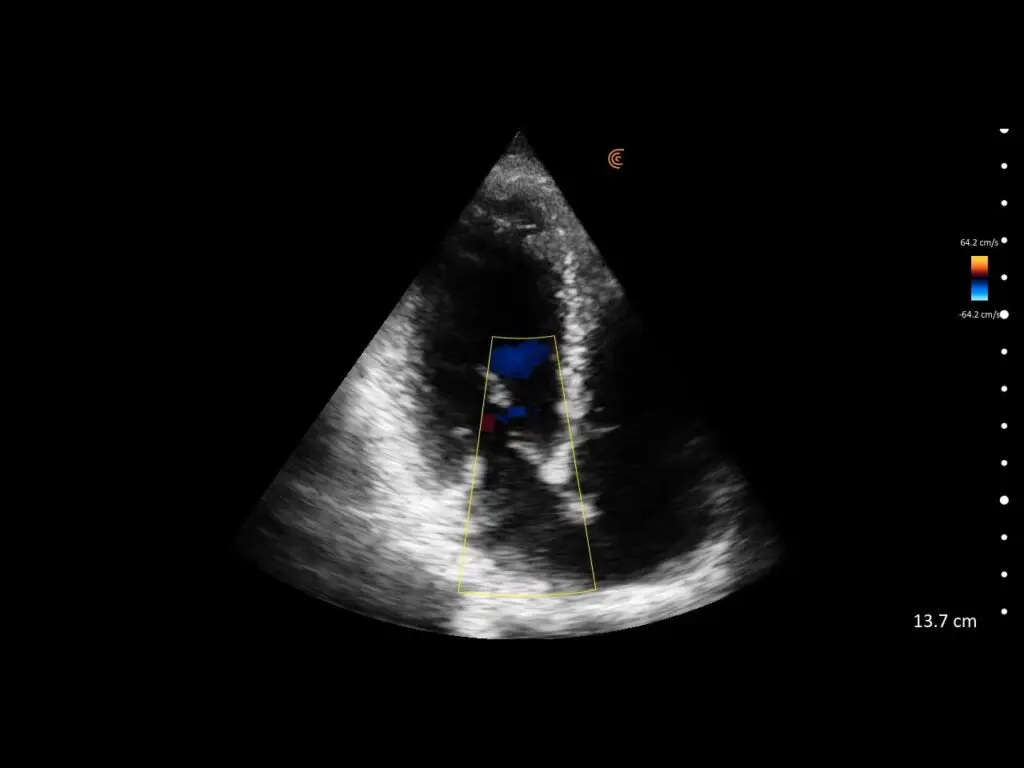

ProbeFix Dynamic is a new device that enables high-quality ultrasound measurements during dynamic exercise by keeping an ultrasound probe in place, allowing for muscle monitoring during intense movement and creating new research possibilities in muscle imaging.